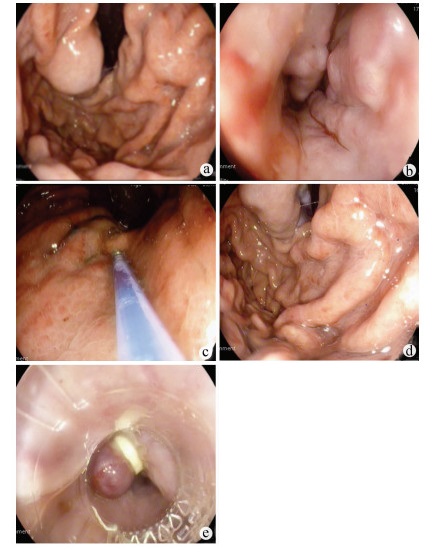

以亚急性肝衰竭为首发表现的IgG4相关性自身免疫性肝炎1例报告

蒋黎, 刘慧敏, 毛青

2022, 38(1): 170-173. DOI: 10.3969/j.issn.1001-5256.2022.01.028

摘要(1579) HTML (431) PDF (3941KB)(84)

摘要: